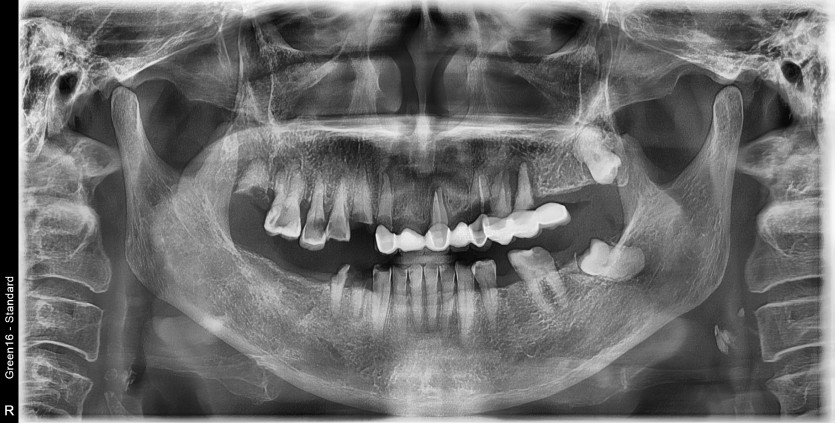

상악 전체 임플란트 증례입니다.(하악 일부)

15개의 임플란트로 완성하였습니다.